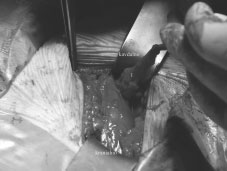

Sl. 2. Desnostranska Spigelijeva kila.

Figure 2. Rightsided Spigelian hernia.

Sl. 3. Anatomija desnostranske Spigelijeve kile. 1 €“ kilna vreča, 2 €“ desna prema trebušna mišica (musculus rectus abdominis dexter), 3 €“ desna zunanja poševna trebušna mišica (musculus obliquus externus abdominis dexter).

Figure 3. Anatomy of right-sidedSpigelian hernia. 1 €“ hernia sac, 2 €“ righsided rectus abdominis muscle, 3 €“ rightsided obliquus externus abdominis muscle.

69-letni moški je v stoječem položaju približno dve leti opažal dva centimetra veliko kilo, ki se je postopno večala in ga pričela ovirati pri vsakdanjih opravilih (Sl. 2). Prej so mu odstranili slepič, zato smo najprej pomislili na pooperativno kilo, ki pa je po apendektomiji redka (0,12 %) (2). Zaradi klinično očitne kile slikovnih diagnostičnih preiskav nismo opravljali. Pri operaciji smo ugotovili defekt trebušne stene z razmaknjenimi vitrami fascije v področju Spigelijeve polkrožne črte. Mesto je bilo nekaj centimetrov bolj medialno od brazgotine po apendektomiji, zato smo z gotovostjo izključili pojav pooperativne kile. V defektu trebušne stene je bila najdena kilna vreča, v kateri je bilo preperitonealno maščevje (Sl. 3). Po repoziciji kile v trebušno votlino smo naredili hernioplastiko s polipropilensko mrežico, ki smo jo vstavili preperitonealno in pritrdili s posameznimi šivi. Preko mrežice smo zašili duplikaturo fascije zunanje poševne trebušne mišice (musculus obliquus externus abdominis). Razen manjšega podkožnega hematoma, ki se je resorbiral spontano, je bil pooperativni potek gladek.